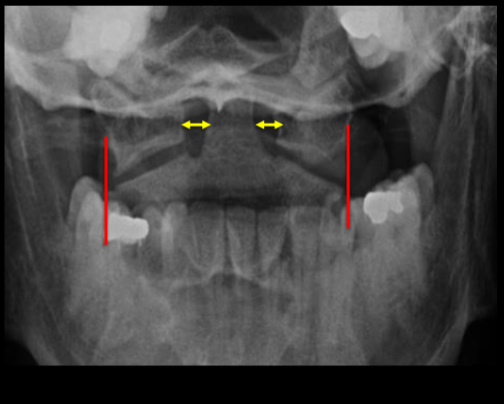

What should antlantoaxial joints appear like in a radiograph?

The lateral borders of the lateral

masses of C1 should align with the

lateral borders of C2.

• The spaces either side of the odontoid

peg should be equal

What is a Jefferson fracture?

Results from a blow to the vertex of the

skull.

• Axial forces are transmitted symmetrically

through the cranium into the superior

surfaces of the lateral masses

• Results in bilateral, symmetrical fractures

of the anterior and posterior arches of C1.

• Demonstrated on the peg view by

displacement of the lateral masses of C1.